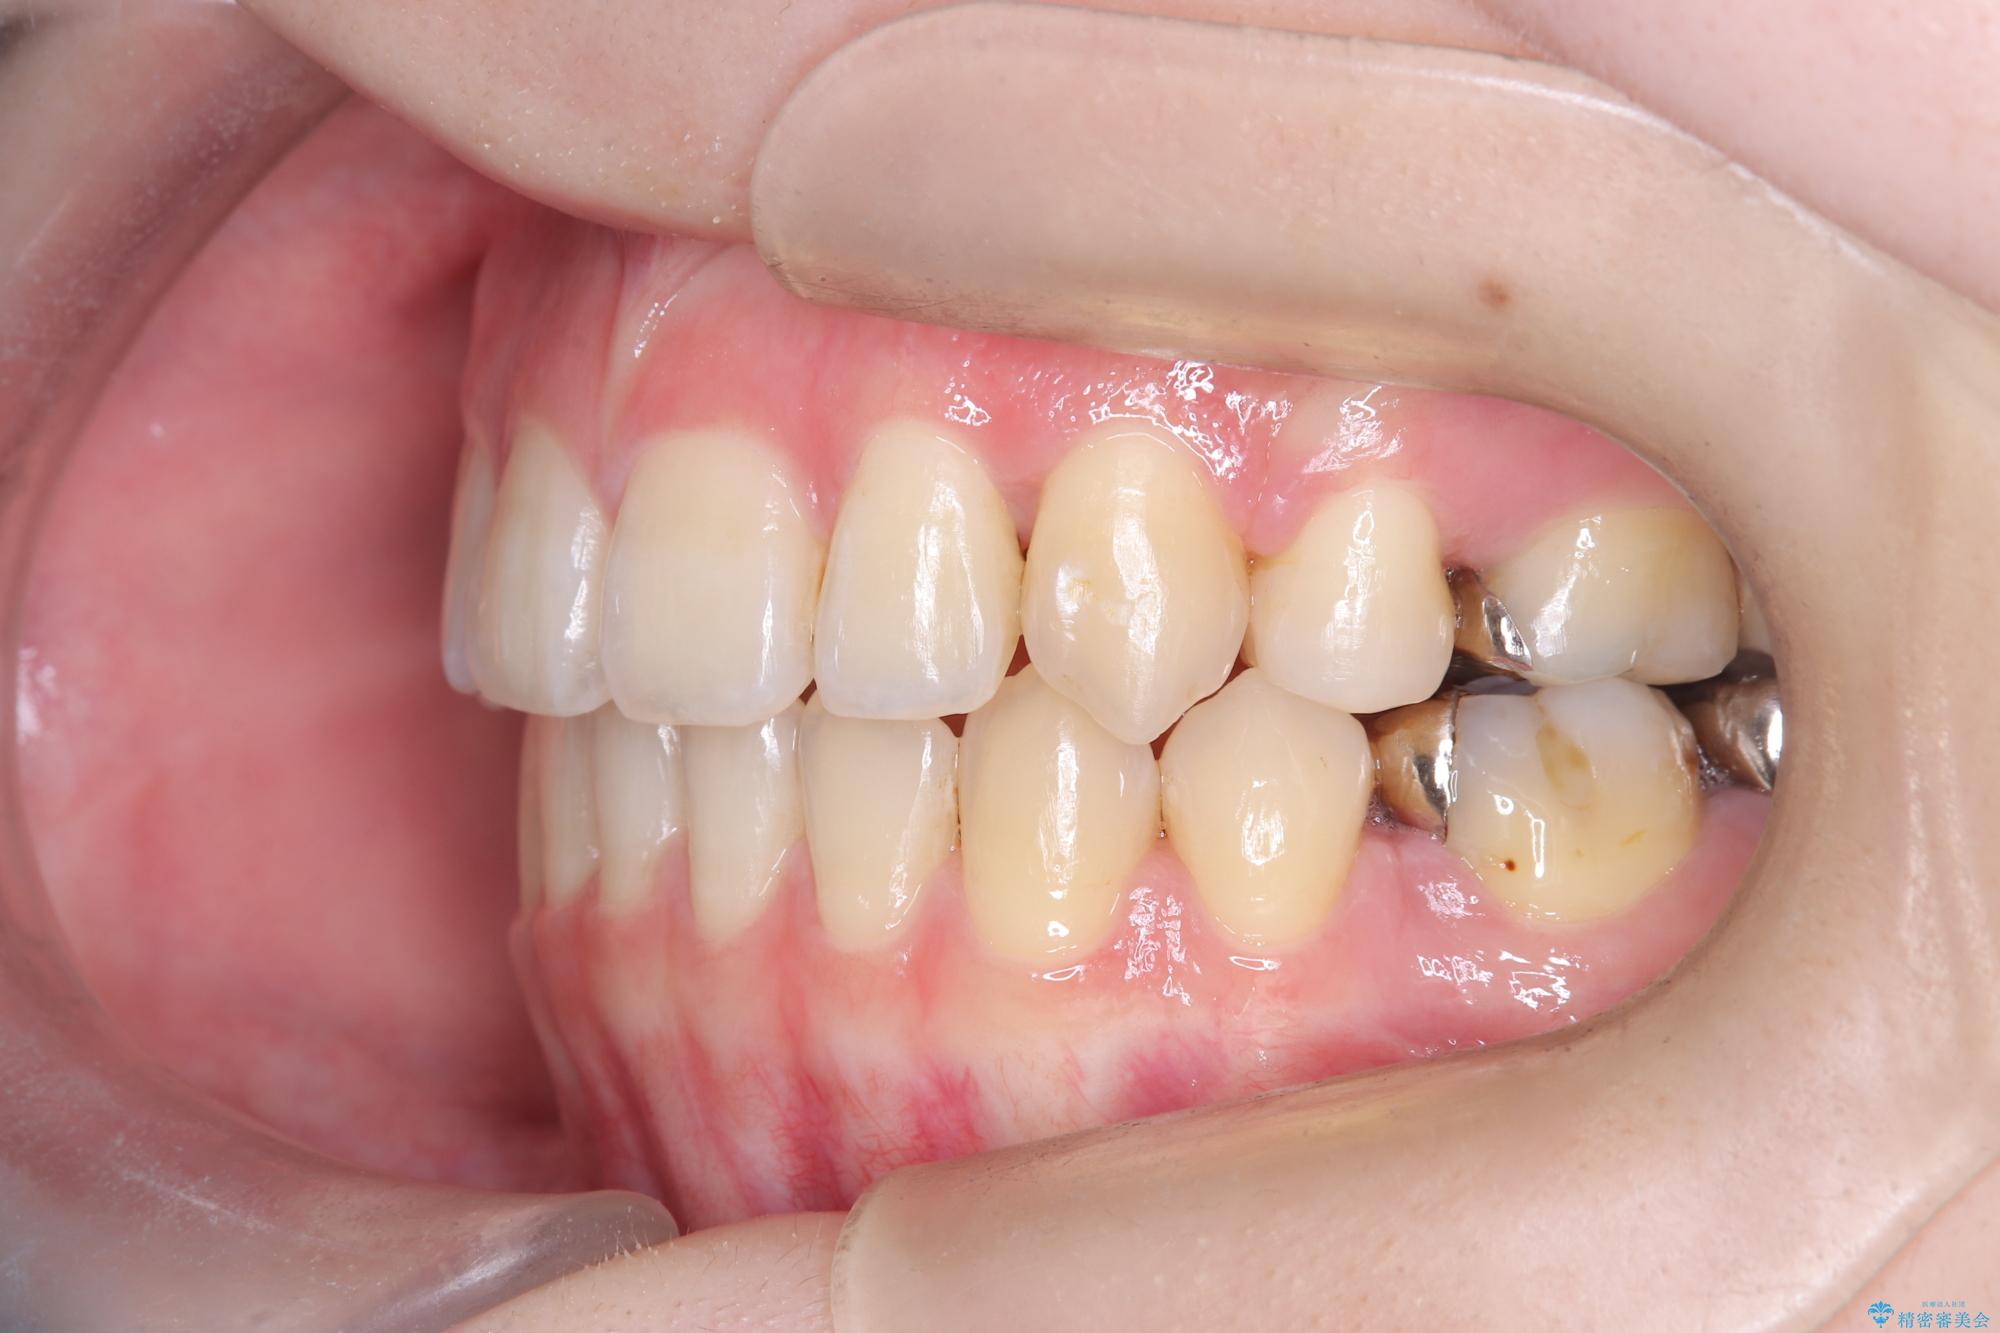

- 開咬と歯のデコボコ(叢生)、八重歯を主訴にご来院された患者様です。

矯正の精密検査の結果、上顎左右4番および下顎左右5番の計4本を抜歯し、ワイヤー矯正(クリア装置)にて治療を行いました。

虫歯があったので、虫歯治療は矯正前に行っています。